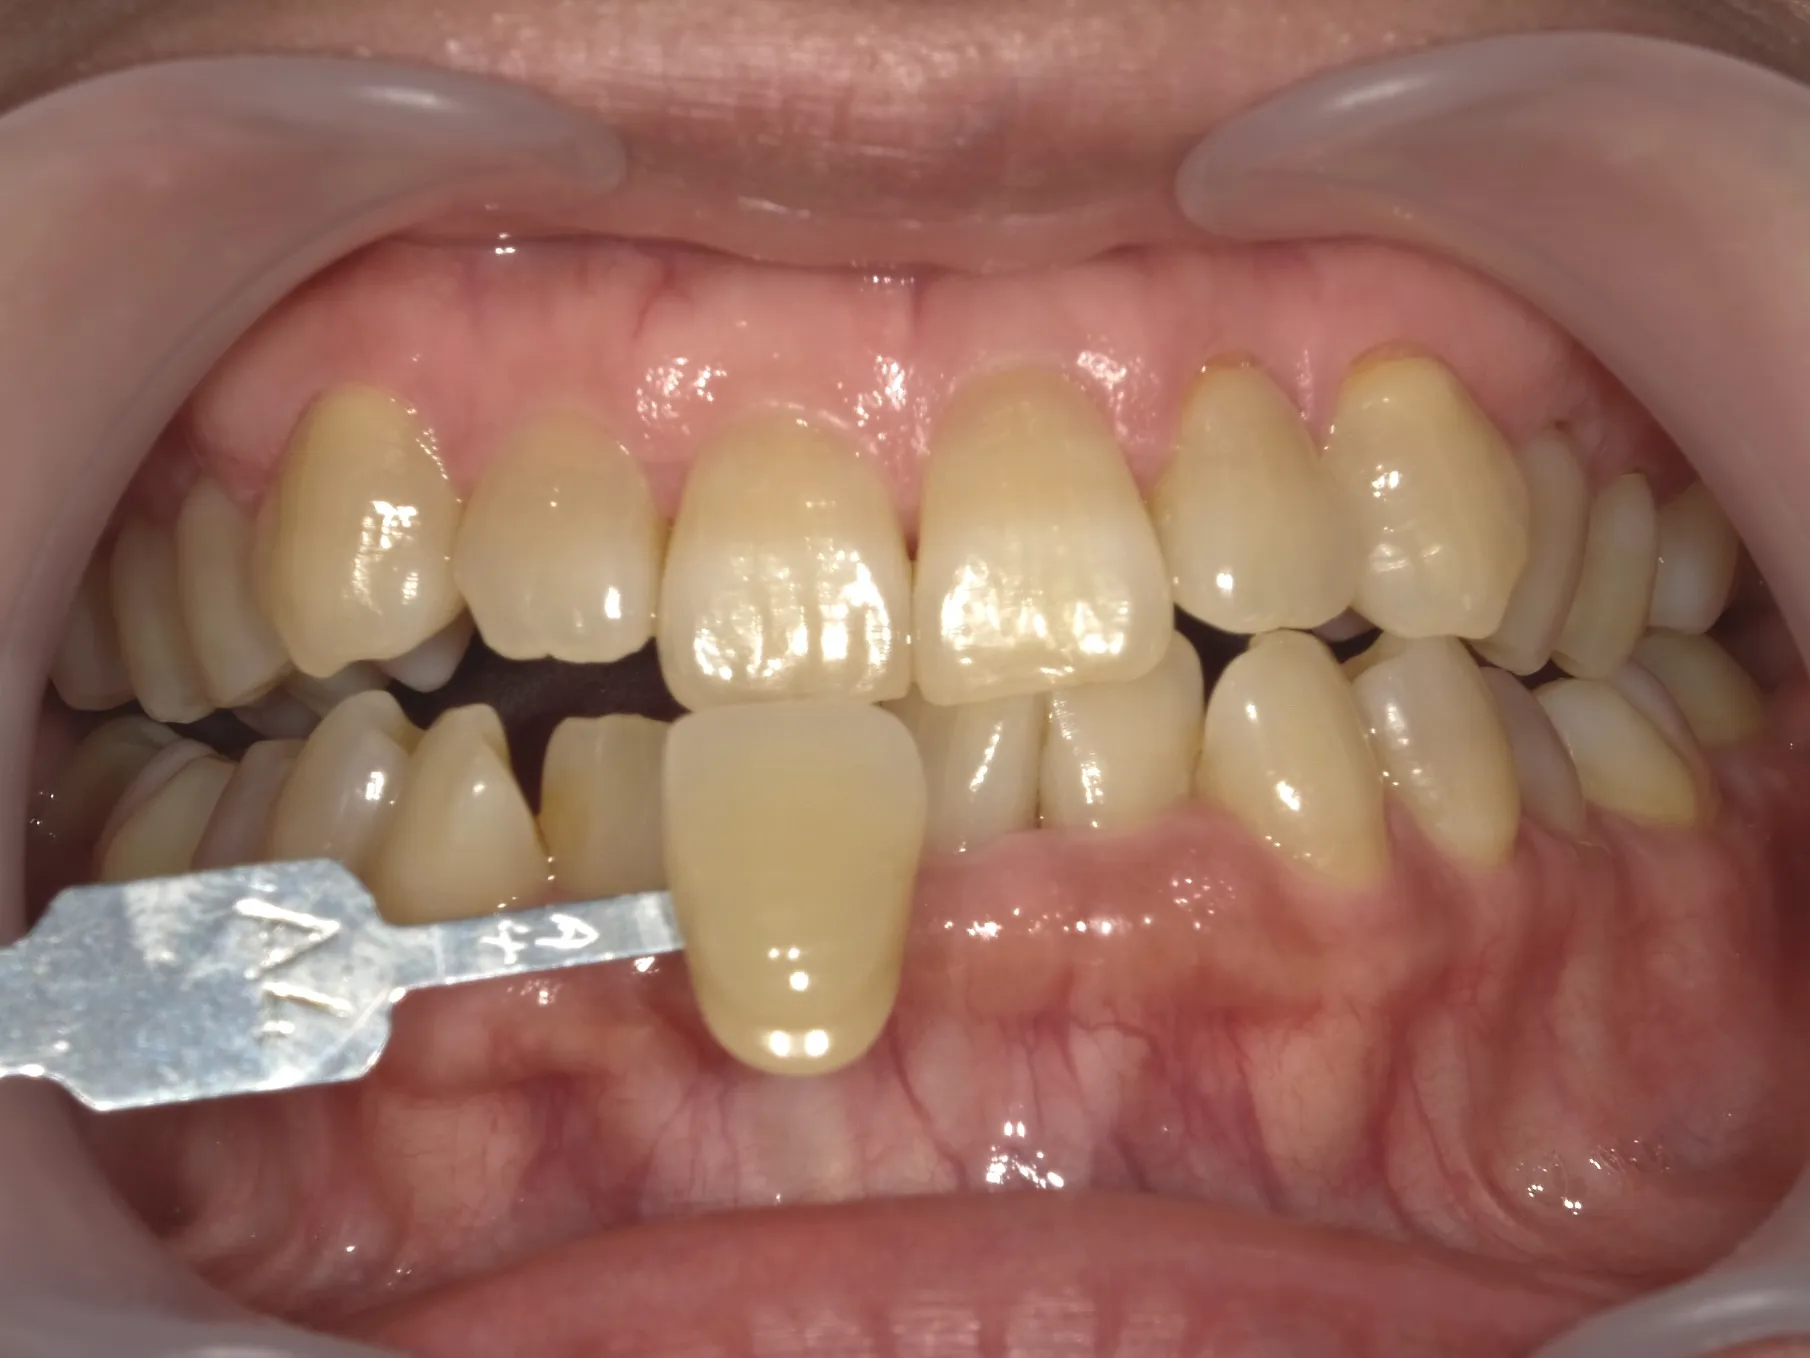

深い着色

テトラサイクリン歯は、黄色から茶色、時には灰色の着色を示すことがあります。

この着色は歯の表面だけでなく、内部にまで及ぶことが特徴です。

不均一な着色パターン

テトラサイクリン歯の着色は歯全体に均等に現れるわけではありません。

歯によってはバンド状、斑点状、または不規則なパターンで現れることが特徴です。

テトラサイクリン歯の治療法

テトラサイクリン歯の治療には、以下の方法が一般的に用いられます。